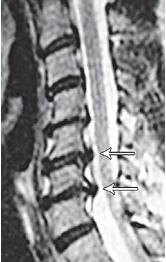

МРТ № 1

На магнитно-резонансной томографии (МРТ) № 1 — шейный отдел позвоночника, в относительно нормальном состоянии.

Шейный отдел позвоночника должен иметь нормально выраженный физиологический лордоз, не должно быть гиполордоза или гиперлордоза, а так же кифотических деформаций.

Ширина спинного мозга: сагиттально > 6–7 мм

1. Сагиттальный размер позвоночного канала на уровне:

СI 21 мм

СII 20 мм

СIII 17 мм

CIV-CVII = 14 мм

2. Высота межпозвонковых пространств:

СII < СIII < СIV < СV < СVII  СVII

3. Ширина спинномозгового канала: поперечный диаметр на уровне ножек: > 20–21 мм